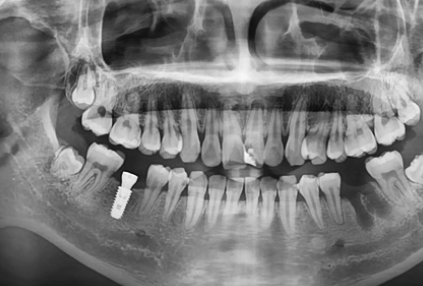

< Some implant surgery cases >

Treatment period: 24.11.3 - 24.12.3

Problem tooth location: tooth no. 46